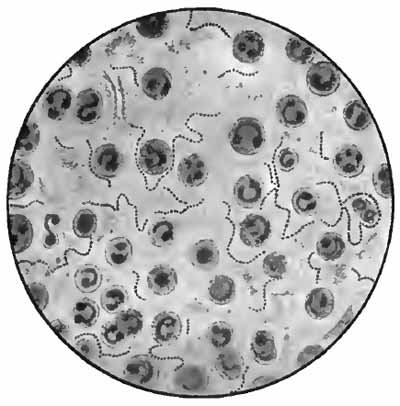

Bacillus of influenza

FIG. 11.—Bacillus of influenza; cover-glass preparation of sputum from a case of influenza, showing the bacilli in leukocytes; highly magnified (Pfeiffer).

(5) Bacillus of Influenza.—This is the etiologic factor in true influenza. It is present, often in large numbers, in the nasal and bronchial secretions, and is also found in the local lesions following influenza. Chronic infection by influenza bacilli may be mistaken clinically for tuberculosis, and they should be searched for in all cases of obstinate chronic bronchitis.

Their recognition depends upon the facts that they are extremely small bacilli; that most of them lie within the pus-cells; that their ends stain more deeply than their centers, sometimes giving the appearance of minute diplococci; and that they are decolorized by Gram's method of staining (Fig. 11).

They are stained blue in Gabbet's method for tubercle bacilli, but are more certainly recognized by Smith's method or by Gram's method, followed by Bismarck brown or fuchsin, as follows: